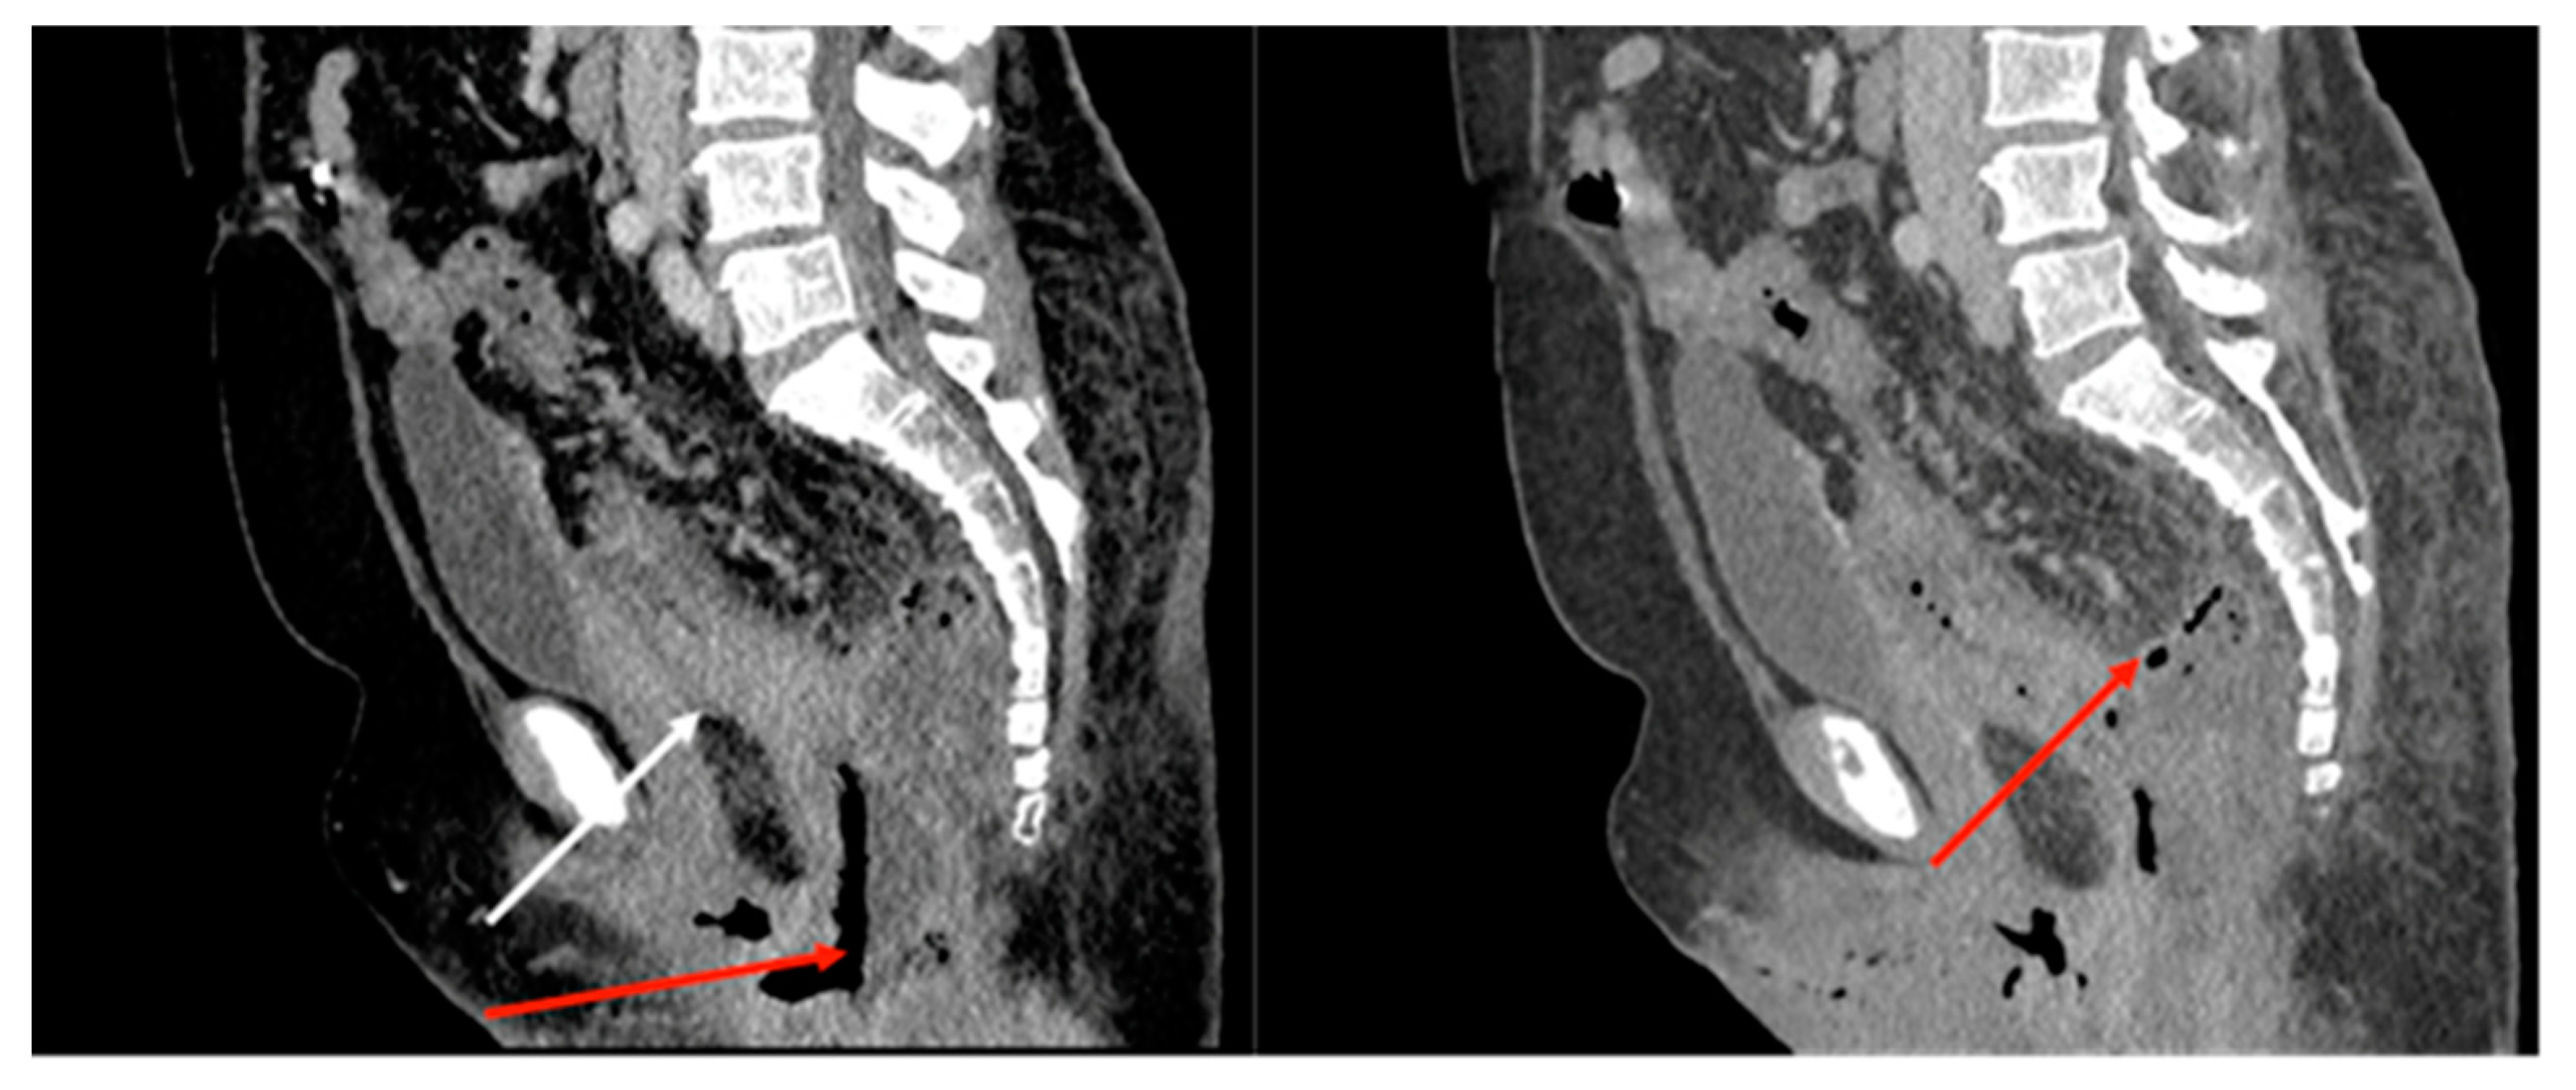

2.1. Case Report